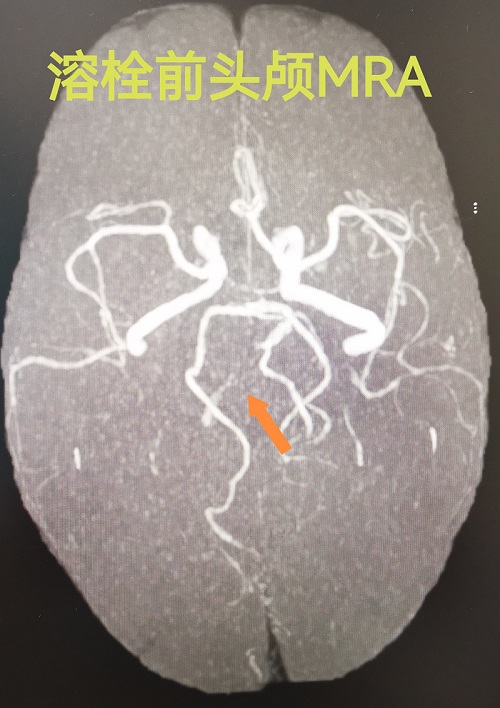

时间回到2025年3月15日,51岁的程先生因“突发意识不清1小时10分钟”被紧急送至兰陵县人民医院急诊科到院时已陷入昏迷状态,并伴有恶心、呕吐症状。情况危急!卒中中心立即启动绿色通道,急查头颅CT排除脑出血后,进一步行头颅磁共振检查,明确诊断为:右侧桥脑、双侧小脑急性脑梗死,右侧椎动脉远端闭塞。

溶栓前右侧椎动脉闭塞.jpg